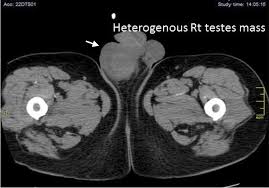

This was the case recently for a client who was diagnosed with testicular cancer and later died after having chemotherapy treatment. He was first seen in April 2016 with swollen testicles and the GP diagnosed him with orchitis infection. He was prescribed with antibiotics. Client was then seen a few times by his GP in relation to an ankle fracture through the summer period of 2016. During this period no complaints were brought to the attention of the GP.

He was seen again in October 2016 regarding painful and swollen testicles, the GP believed it was a re-current infection and on the second visit in October he was referred for an Ultrasound scan to rule out any serious causes such as cancer. Unfortunately, the client failed to book his ultrasound scan and after 2 reminders from the NHS, his referral was cancelled. He then went back to his GP and was re-referred in December for an urgent scan which then lead to a diagnosis of cancer.